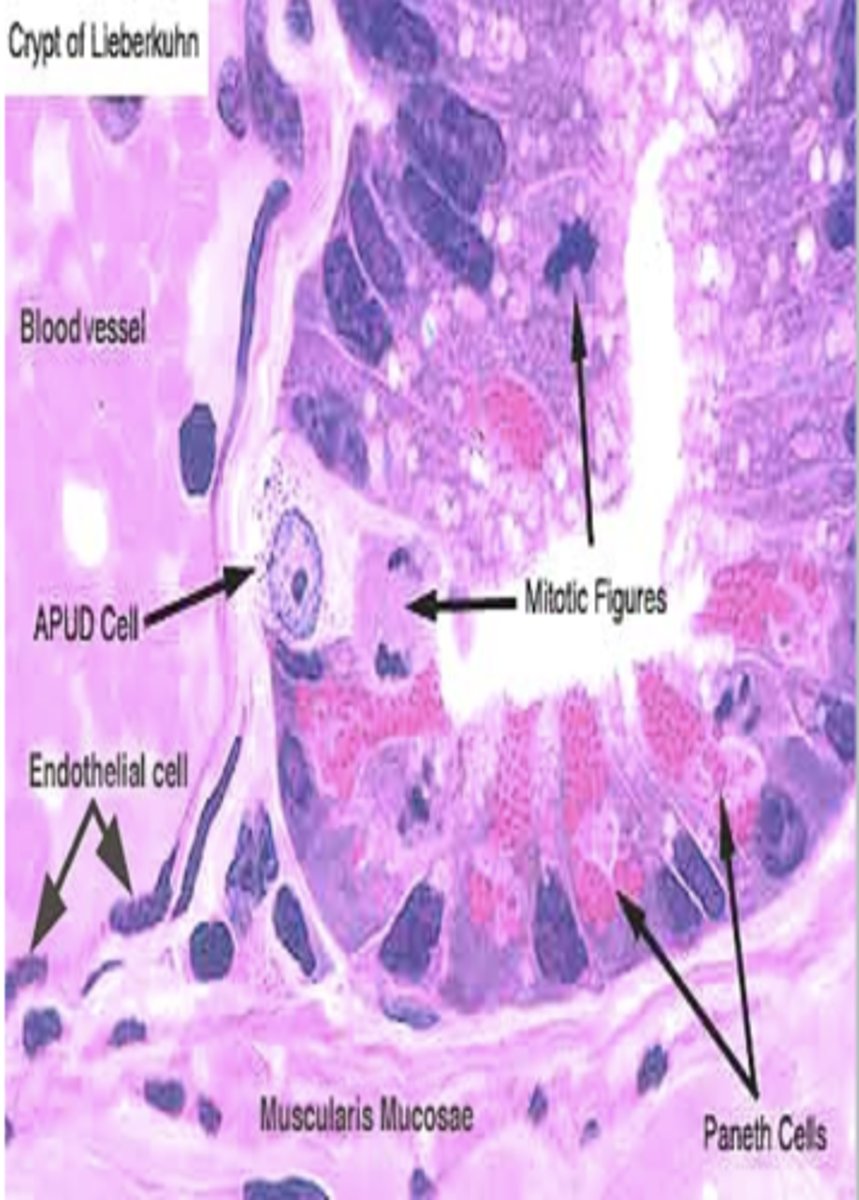

Crypts of Lieberkuhn

− Deep pits/invaginations formed by mucosal folds

- mainly in small intestine

− Contain villi for absorption

- Contains several types of secretory cells, including Goblet cells and enterocytes

Crypts of Lieberkuhn Function

Goblet cells and enterocytes secrete:

- digestive enzymes

- H2O

- ions

- Mucus

facilitate lubrication, digestion and absorption

APUD cells

− Single-cell mucosal endocrine glands

- mainly small intestine

APUD cells Function

Secrete various GI hormones

- endocrine regulation of GI functions